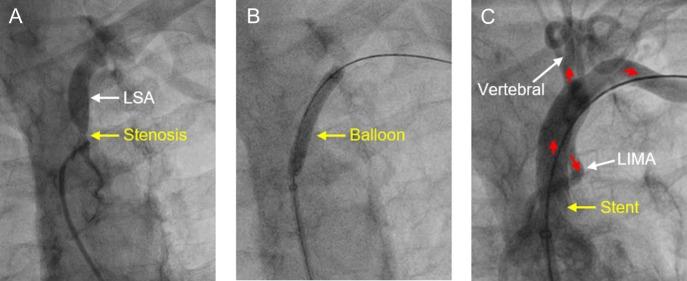

Subclavian artery stenosis (SAS) resulting in coronary subclavian steal syndrome (CSSS) is a common but under recognized pathology following coronary artery bypass surgery (CABG). Patients with SAS may be asymptomatic due to the sub-clinical diversion of blood flow from the myocardium and retrograde blood flow during catheter angiography in the left internal mammary artery (LIMA) may be the first suggestion of CSSS. The management of SAS, causing CSSS, may rarely require acute assessment and intervention. However, full anatomical assessment of the stenosis morphology may be limited on fluoroscopy. Correction of SAS may be essential to achieve effective reperfusion therapy.